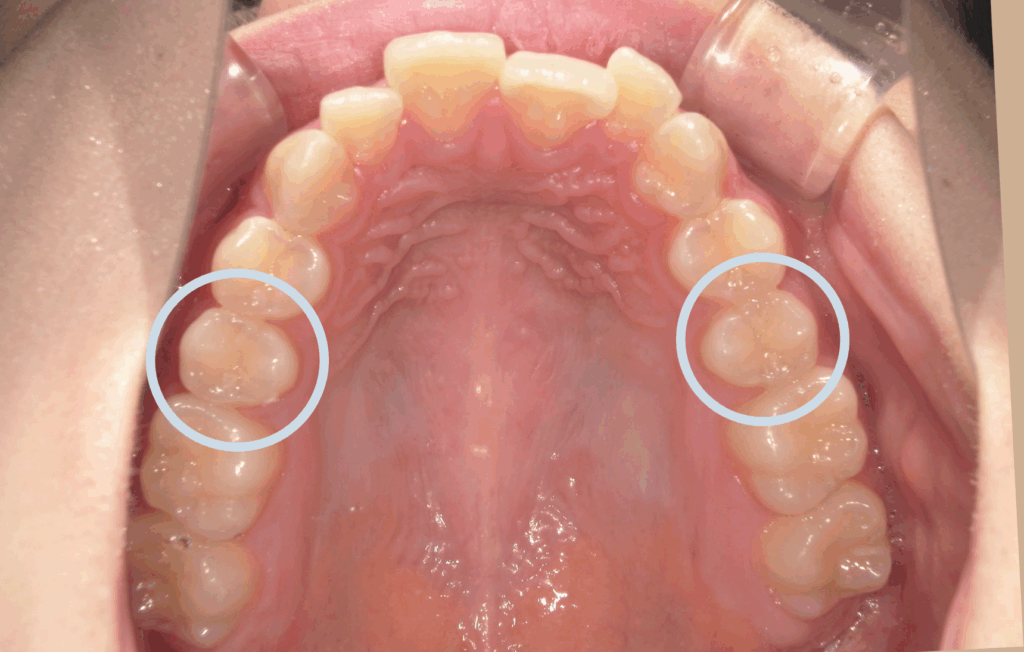

<初診時>

上の前歯の横の歯(前から2番目)が前方に飛び出しており、全体的にガタつき(叢生)が見られます。これは、歯の大きさに対してあごの幅がやや狭く、歯がきれいに並ぶスペースが足りないために起こります。

また、上下の前歯の中心(正中線)がわずかにずれており、奥歯のかみ合わせやあごの位置の影響がみられました。

上の前歯1本が前に出ており、いわゆる「出っ歯」の状態です。見た目の印象だけでなく、口を閉じにくい・前歯で噛みにくいなどの機能面への影響もありました。